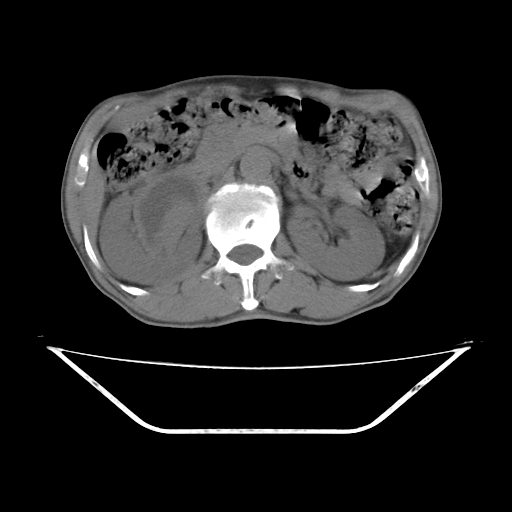

增强

考虑右肾盂癌,肾动脉受侵,右肾功能减退,右肾盂输尿管积水,管壁增厚,考虑种植转移,应该把下面扫完的

支持右侧肾盂癌伴肾静脉瘤栓形成可能性大,右肾结石.肝右叶后段低密度影,不除外转移.

右肾盂旁ca并肾静脉瘤栓形成/肾功能降低。

右肾结石。

右肾盂癌,肾动脉受侵,右肾盂输尿管积水,管壁增厚,考虑种植转移

支持 右侧肾盂癌伴肾静脉瘤栓形成可能性大,右肾结石;肝右叶后段低密度影,不除外转移。

1.右侧肾盂癌伴肾盂积水。

2.肾脏功能减退,原因有:(1)肾动脉受侵。(2)肾静脉受侵(3)肾积水,等。本例,肾动脉显影较好,但受压明显;肾静脉无明显显示,受压或静脉癌栓,下腔静脉腔内未见明显充盈缺损。

3.右侧上段输尿管扩张,原因:(1)积水所致;(2)种植。